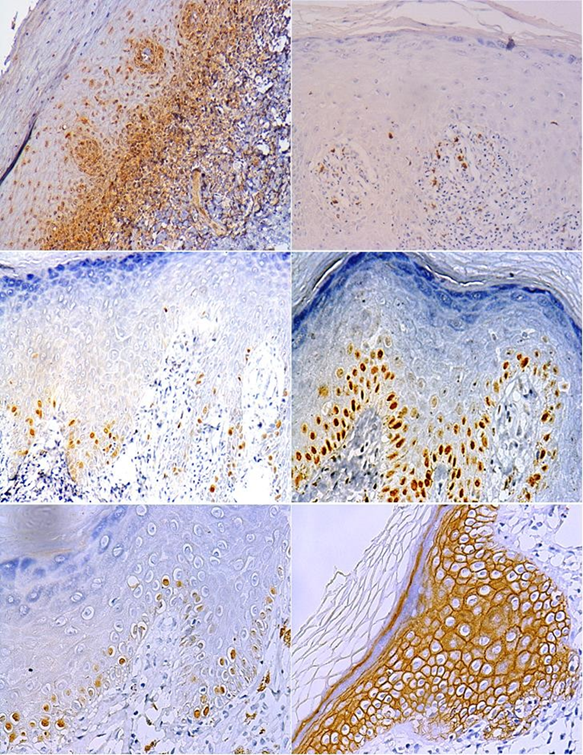

The expression of apoptosis-related markers, as is the case of BAX, was predominantly weak for 50% of samples, localized in the basal layer of the epithelium, and found in the cytoplasm of basal keratinocytes (Fig. 1. A), while BCL-2 showed weak cytoplasmic expression with 42.86% of cases, in suprabasal layers, away from the area of lymphocytic attack; the nuclear expression of p53 observed was predominantly negative, since 81.4 % of the samples showed a positivity average lower than 4% and whereas the remaining 18.60% showed a weak presence of p53 in the band-like subepithelial infiltrate, this could be an indication of apoptotic activity in these parts of the tissue, as well as the presence of cell damage in the basal layer, and the weak expression could be explained by the rapid proteolysis of this protein, as well as the fact that it is only involved during the G1 phase of the cell cycle (Fig. 1. B).

The average cell proliferation index at the nuclear level for Ki-67 was 12.40%, and proliferative cells were observed mainly in the basal layer of the epithelium (Fig. 1. C), while MCM3 showed moderate to strong nuclear positivity in almost all cases with average cell proliferation of 33.36% also in basal keratinocytes (Fig. 1. D); in turn, positivity at the nuclear level for histone H3 (H3) was predominantly weak, followed by moderate positivity, with a final average cell proliferation index of 26.76% and also found in the basal layer (Fig. 1. E).

CD-138 was found to be mostly strongly positive, with 95.35% at the level of the cell membrane throughout the epithelium, without negative expression in any of the cases (Fig. 1. F).